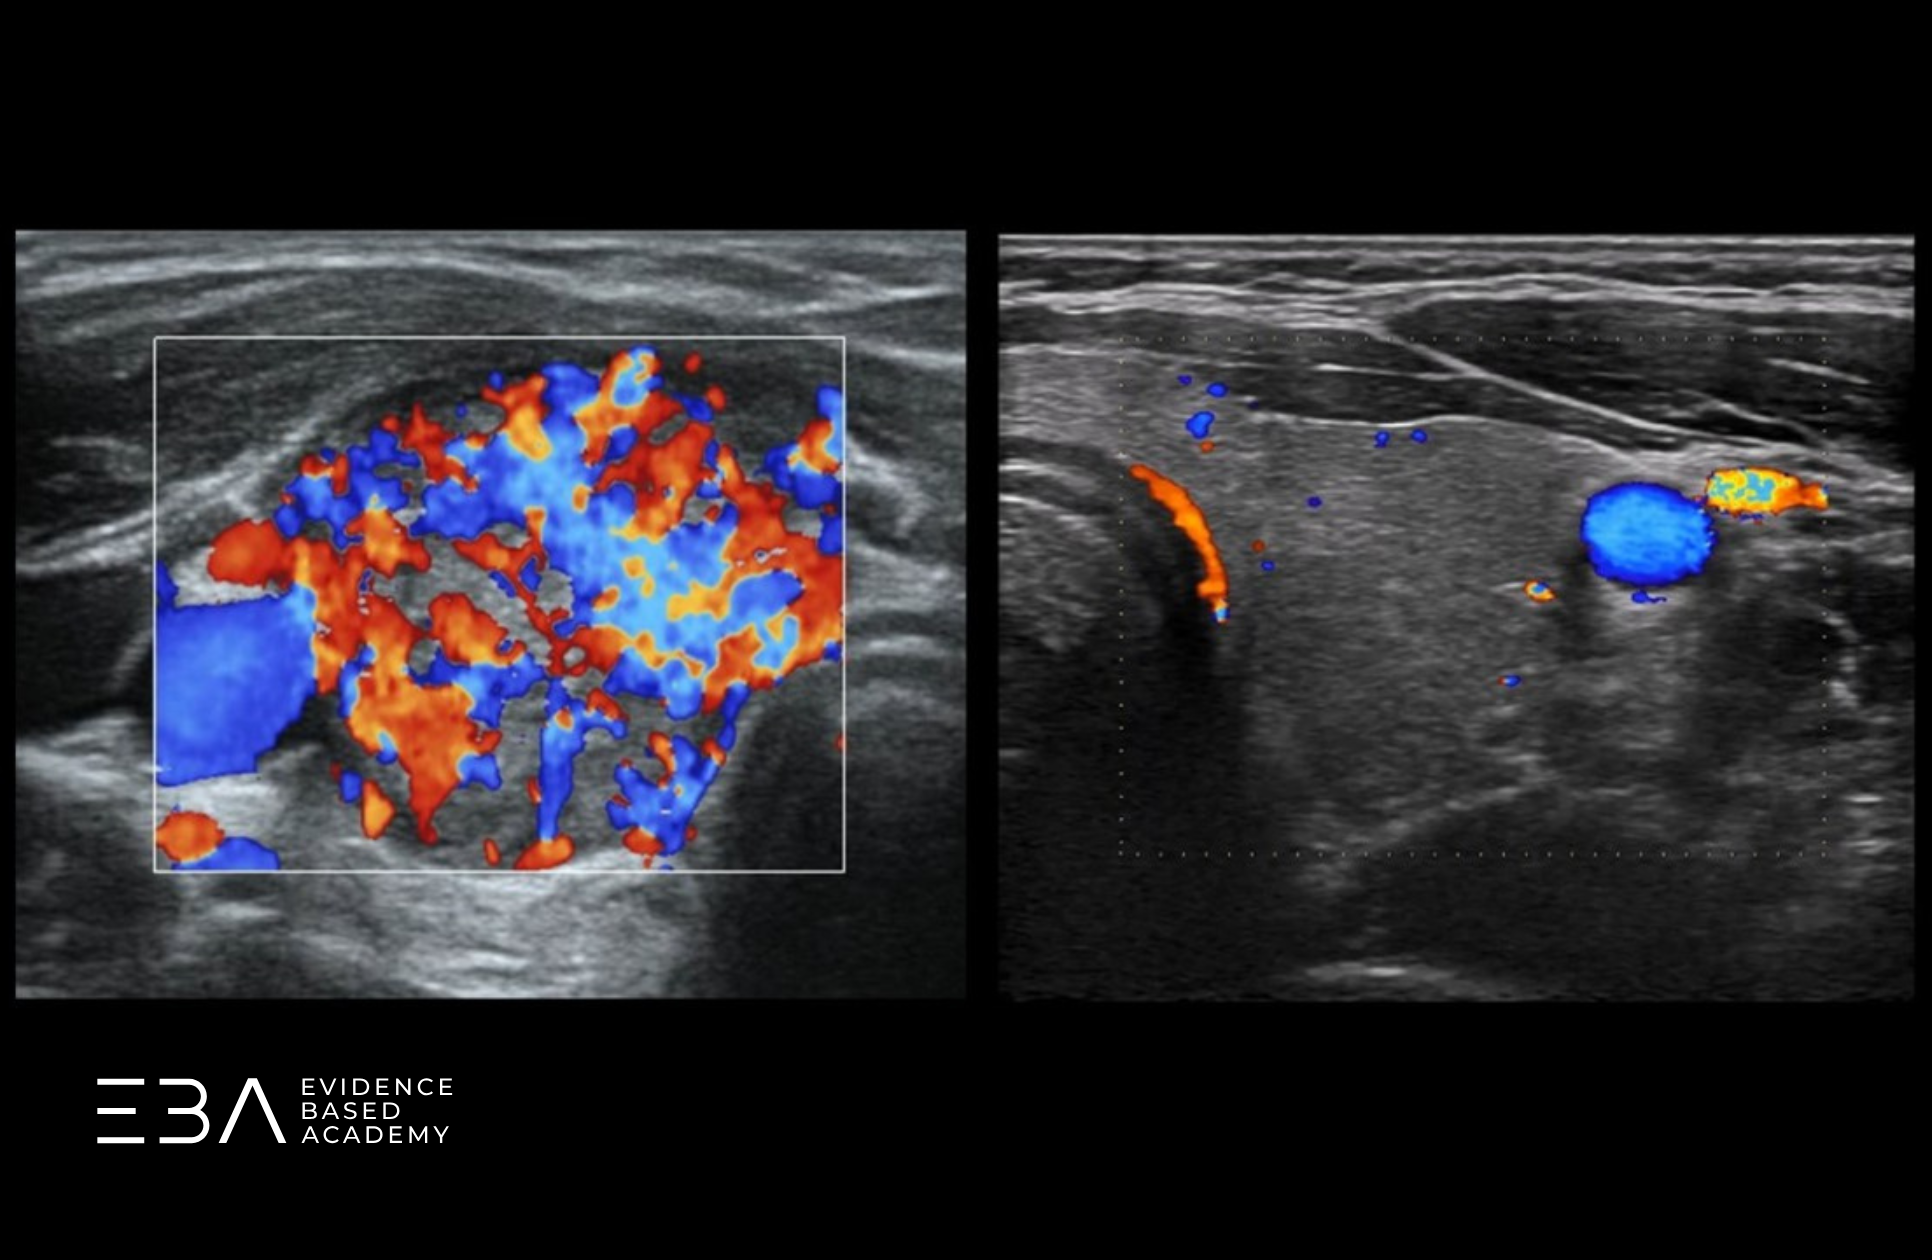

W warunkach prawidłowych unaczynienie tarczycy jest skąpe – na obrazie widoczne są głównie naczynia położone obwodowo (podtorebkowo) i pojedyncze drobne naczynia w środkowej części płata.

Dla porównania – u pacjentów z zapaleniem autoimmunizacyjnym tarczycy zwykle dochodzi do wzmożenia przepływu w miąższu. Unaczynienie jest wówczas bogate i widoczne we wszystkich częściach płata.

Porównanie prawidłowego przepływu (po prawej) i wzmożonego (po lewej).